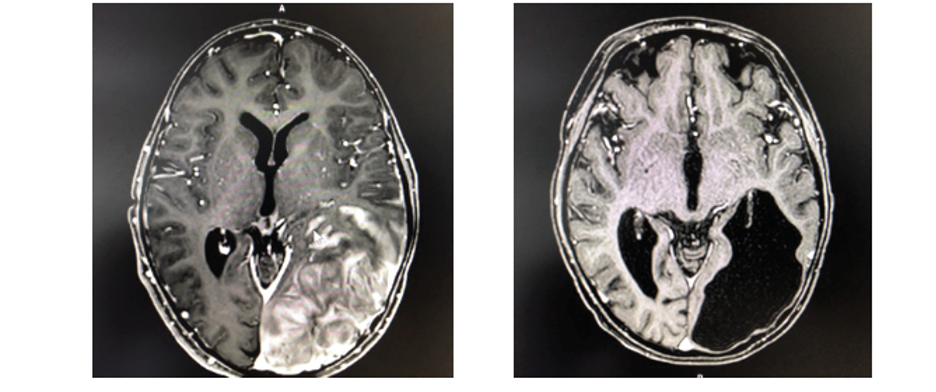

Figure 2. Magnetic Resonance Imaging (MRI) demonstrating regression of leukemic brain infiltration after haploidentical CD19 CAR-T cells infusion resulting in remission of 18 months.

In a landmark proof-of-concept evaluation, domestic CAR-T therapy was successfully administered to an 11-year-old patient facing an exceptionally high-risk clinical scenario. The patient presented with B-cell ALL in its fourth relapse, complicated by extramedullary central nervous system (CNS) involvement—a condition traditionally associated with poor prognosis and limited therapeutic options. This complexity was further compounded by a persistent minimal residual disease-positive (MRD+) status and a history of prior Haploidentical Stem Cell Transplantation.

Notably, the haploidentical allogeneic CAR-T cell infusion demonstrated potent therapeutic efficacy by successfully clearing the leukemic cells within the CNS (Figure 2). The treatment was well tolerated, achieving MRD-negative complete remission within 30 days of administration. Longitudinal data from this initial cohort using allogenenic setting reflects the robust durability of the response, with overall survival (OS) and leukemia-free survival (LFS) rates of 70% and 80%, respectively (Figure 3).